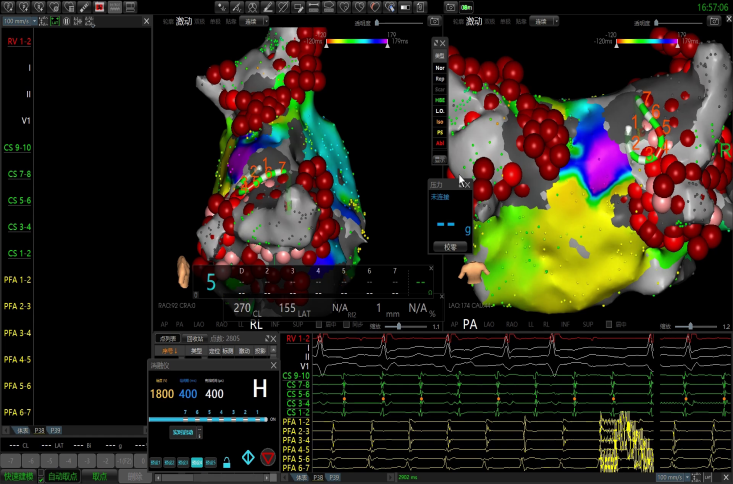

顶部线消融

转为窦性心律。

术后体表&腔内心电图